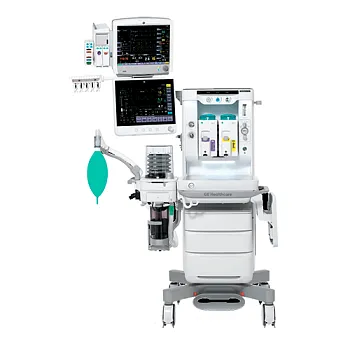

Выгодные комплекты для анестезиологии и реанимации

Официальный дистрибьютор GE HealthСare с 2007 года

Официальный дистрибьютор MINDRAY